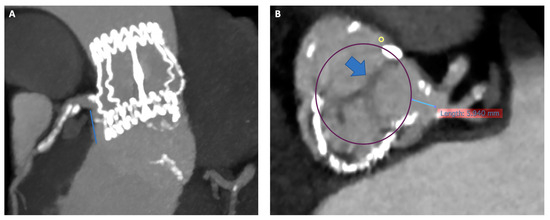

Figure 2.

Risk of coronary artery obstruction evaluation at pre-procedural CT scan. Panel (A) Permissive height of LCA (18 mm). Panel (B) VTC of 5.9 mm simulating a 26 Sapien 3 Ultra with wide Sinus of Valsalva and redundant leaflet. CT, computed tomography; LCA; left coronary artery; VTC, valve to coronary ostia.